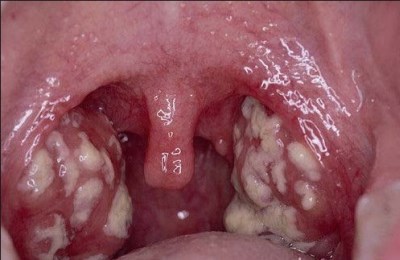

- фарингит хронический или острый;

- гнойная ангина;

- паратонзиллит.

Эти заболевания очень быстро развиваются и являются опасными для пациента, так как при возникновении малейших отеков возможно быстрое нарушение дыхания. При поражении ЛОР-органов часто болит горло.